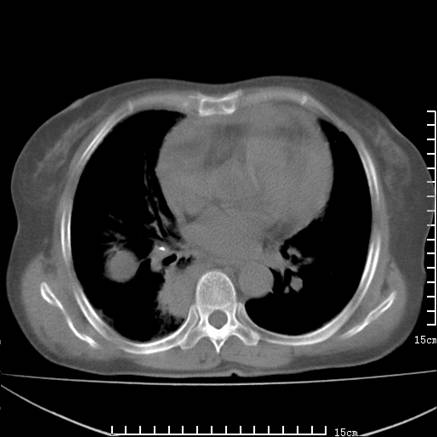

女,王某,58岁,咳嗽三个月余,基层医院二个月前诊为肺结核,用抗结核药二个月无明显疗效。

心包积液致肺瘀血.右侧周围型肺癌伴肺内转移,中间裂积液,叶间胸膜肥厚.右上肺大泡,右侧胸膜肥厚.

双肺继发型tb,心功能不全并肺淤血、心包、双侧叶间裂积液,肺大泡,右下胸膜肥厚钙化。